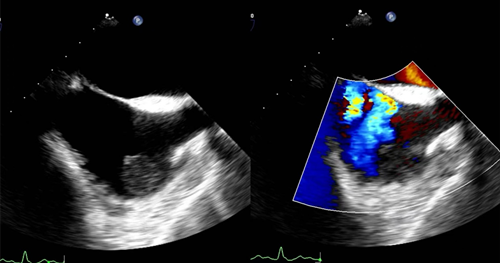

3.先天性心脏病,如:房间隔缺损、卵圆孔未闭等,常规经胸超声声窗差,不易准确诊断的病例,对于经胸超声不能明确房间隔缺损残端大小,或多发房间隔缺损患者,行TEE检查,可明确是否存在封堵适应证,并为封堵器大小的选择提供参考。

(经食管超声显示卵圆孔未闭)

4.心脏瓣膜病:如瓣膜狭窄、关闭不全、脱垂等。

(经食管超声显示二尖瓣反流)